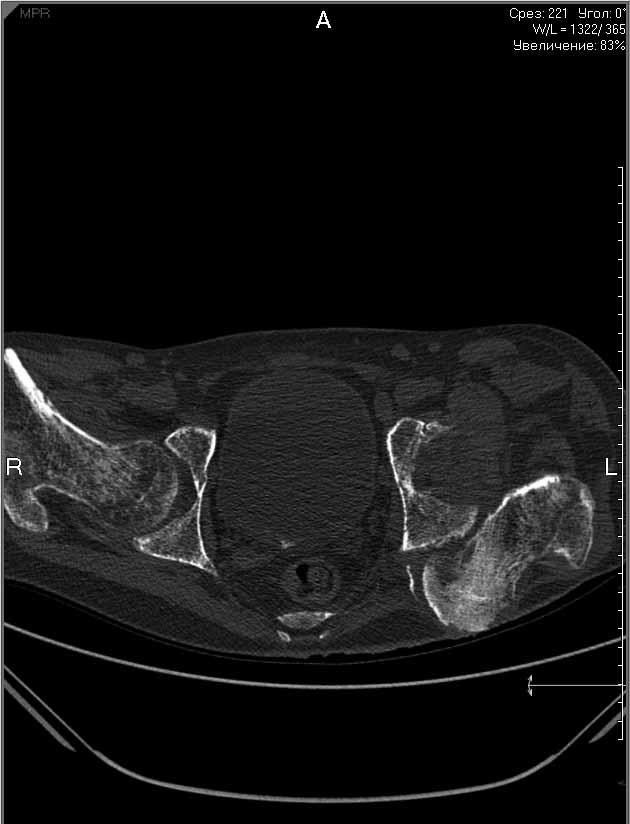

На лечении находится пациент с тяжелой сочетанной травмой. На сегодняшний день встал вопрос о тактике лечения переломов бедер( по месту жительства бедрами не занимались).

Пациенту 22 года. Травма в июле 2010г, лечился в районной больнице. К нам попал в апреле 2011г. Тяжелая сочетанная травма (29.07.2010): тупая травма живота с повреждением внутренних органов. Закрытая травма грудной клетки с переломом ребер. Пневмоторакс справа. Тяжёлая позвоночно-спинномозговая травма. Закрытый осложнённый переломо-вывих С5 позвонка. Верхний парапарез, нижняя параплегия, нарушение функции тазовых органов по типу недержания. Цекостома. Пролежень левой ягодичной области. Неправильно консолидированные переломы верхних третей обеих бедер. Застарелый вывих левого бедра. Осложнение: Поддиафрагамльный абсесс слева, забрюшинного пространства. Свищ желудка и ободочной кишки. Синегнойный сепсис. Двухстороняя пневмония. Но это уже анамнез. Пациент был неоднократно оперирован на органах брюшной полости и осложнениями с ними связанными.

В ягодичной области слева глубокий пролежень размером 2х2см, дном является вывихнутая головка бедра. Неврологически в нижних конечностях динамика положительная, появились движения в правой стопе, чувствительность в стопах. По переломам бедер: подвижности в местах переломов нет, снимки высылаю.

Уважаемые коллеги, помогите определиться с оптимальной тактикой в лечении перелома бедер. Степень оснащенности у нас достаточная (аппараты, штифты, пластины, ЭОП).

Планирую начать с правого бедра, ЧКО таза (передняя рама) с фиксацией бедра. О/клазия места перелома правого бедра и устранение грубых смещений в аппарате. окончательно можно оставить и в аппарате. Далее аппаратное устранение вывиха левого бедра.